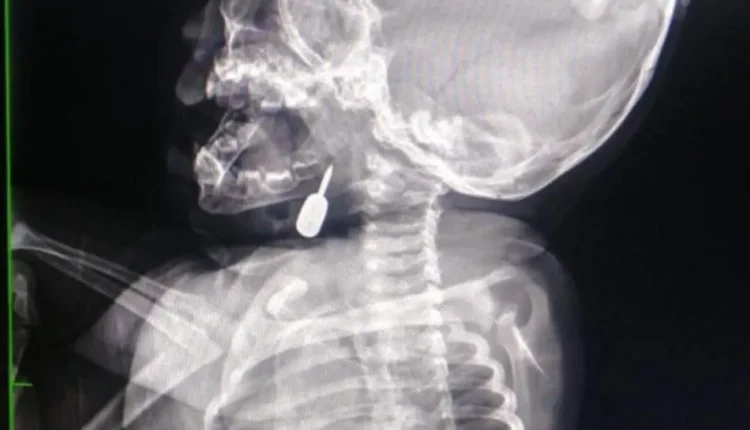

المرفا….تمكّن أخصائي الأنف والأذن والحنجرة الدكتور محمود السبول من إجراء عملية _فتح رغامى_ تُعد الأولى من نوعها في مستشفى الملكة رانيا العبدالله، وقد تمت بنجاح.

وفي تدخل طبي عاجل، أنقذ الدكتور السبول حياة طفل يبلغ من العمر أحد عشر شهراً، بعد أن وصل إلى قسم الطوارئ وهو يعاني من حالة اختناق حادة نتيجة وجود جسم معدني عالق في منطقة الحنجرة. وقد تم استخراج الجسم بنجاح، مما أسهم في إنقاذ حياة الطفل.